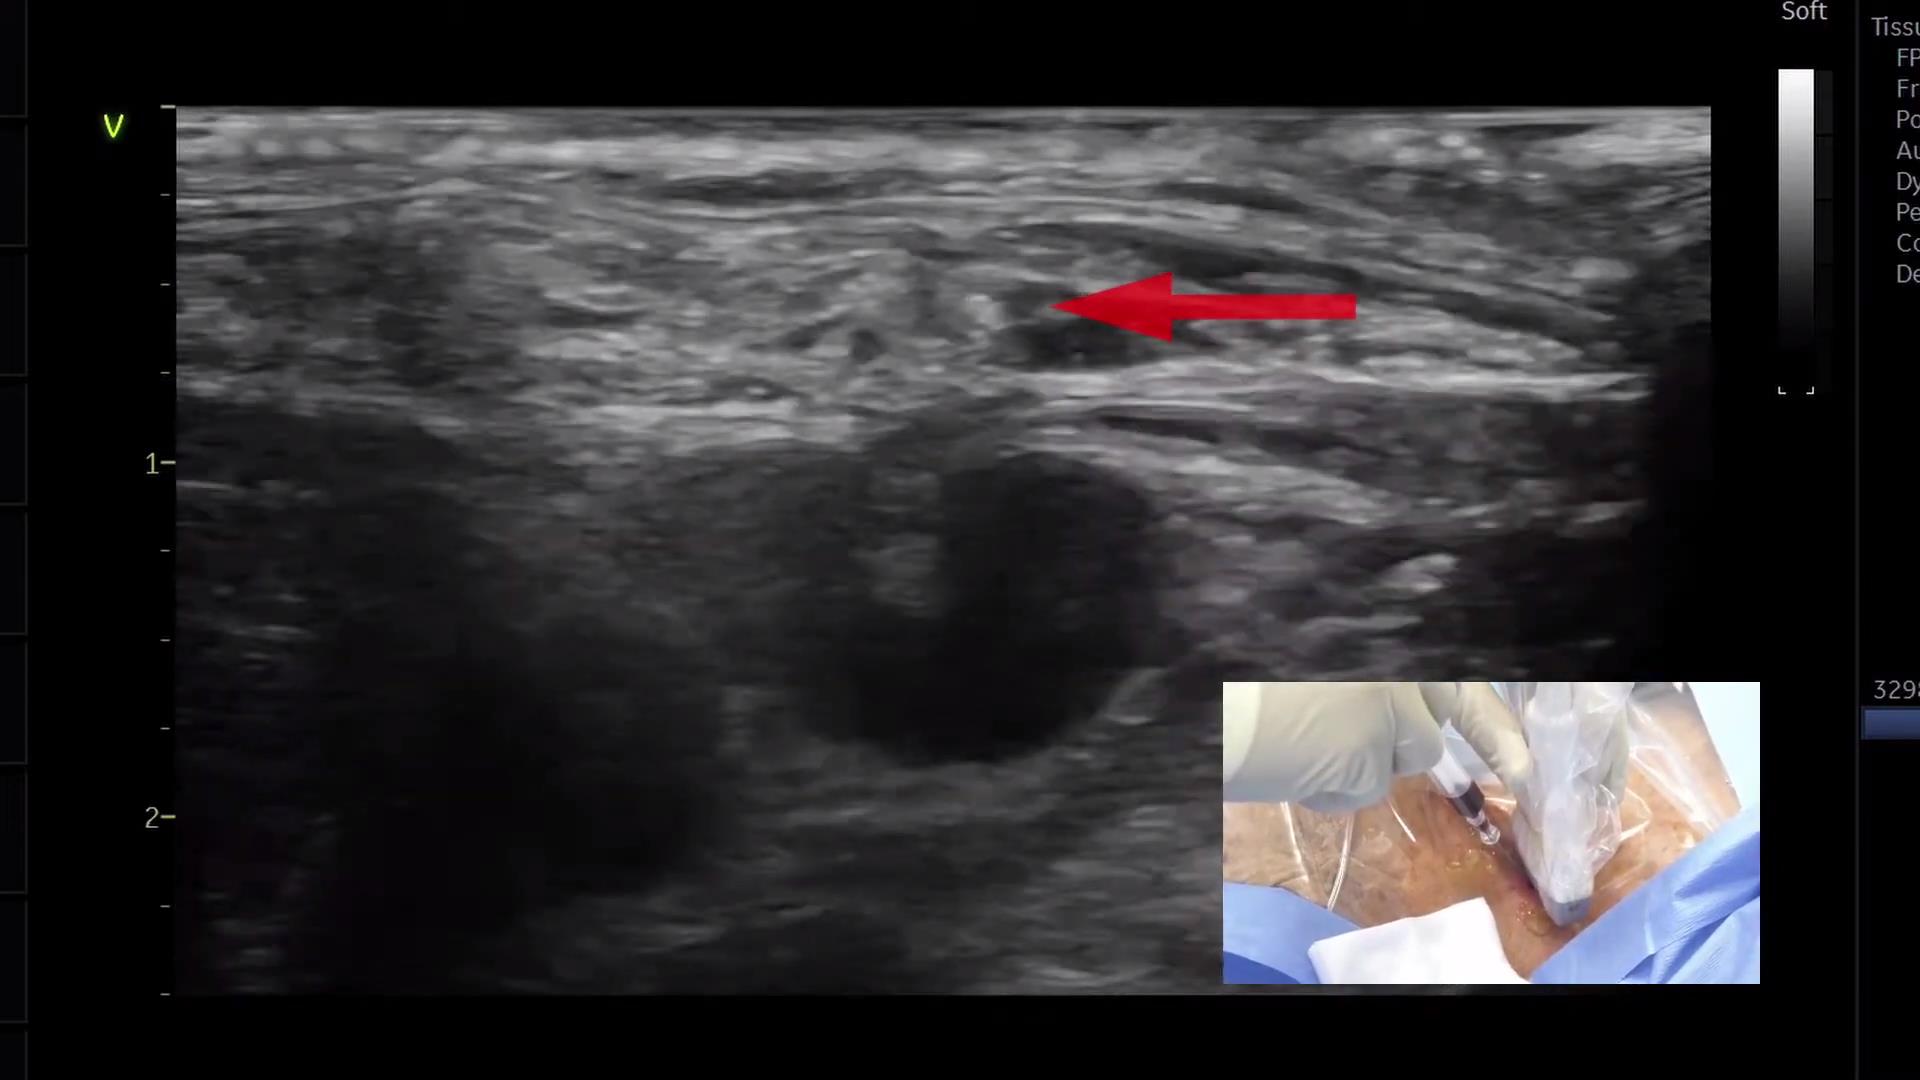

超声引导平面内锁骨下静脉穿刺置管

331 #锁骨下静脉穿刺